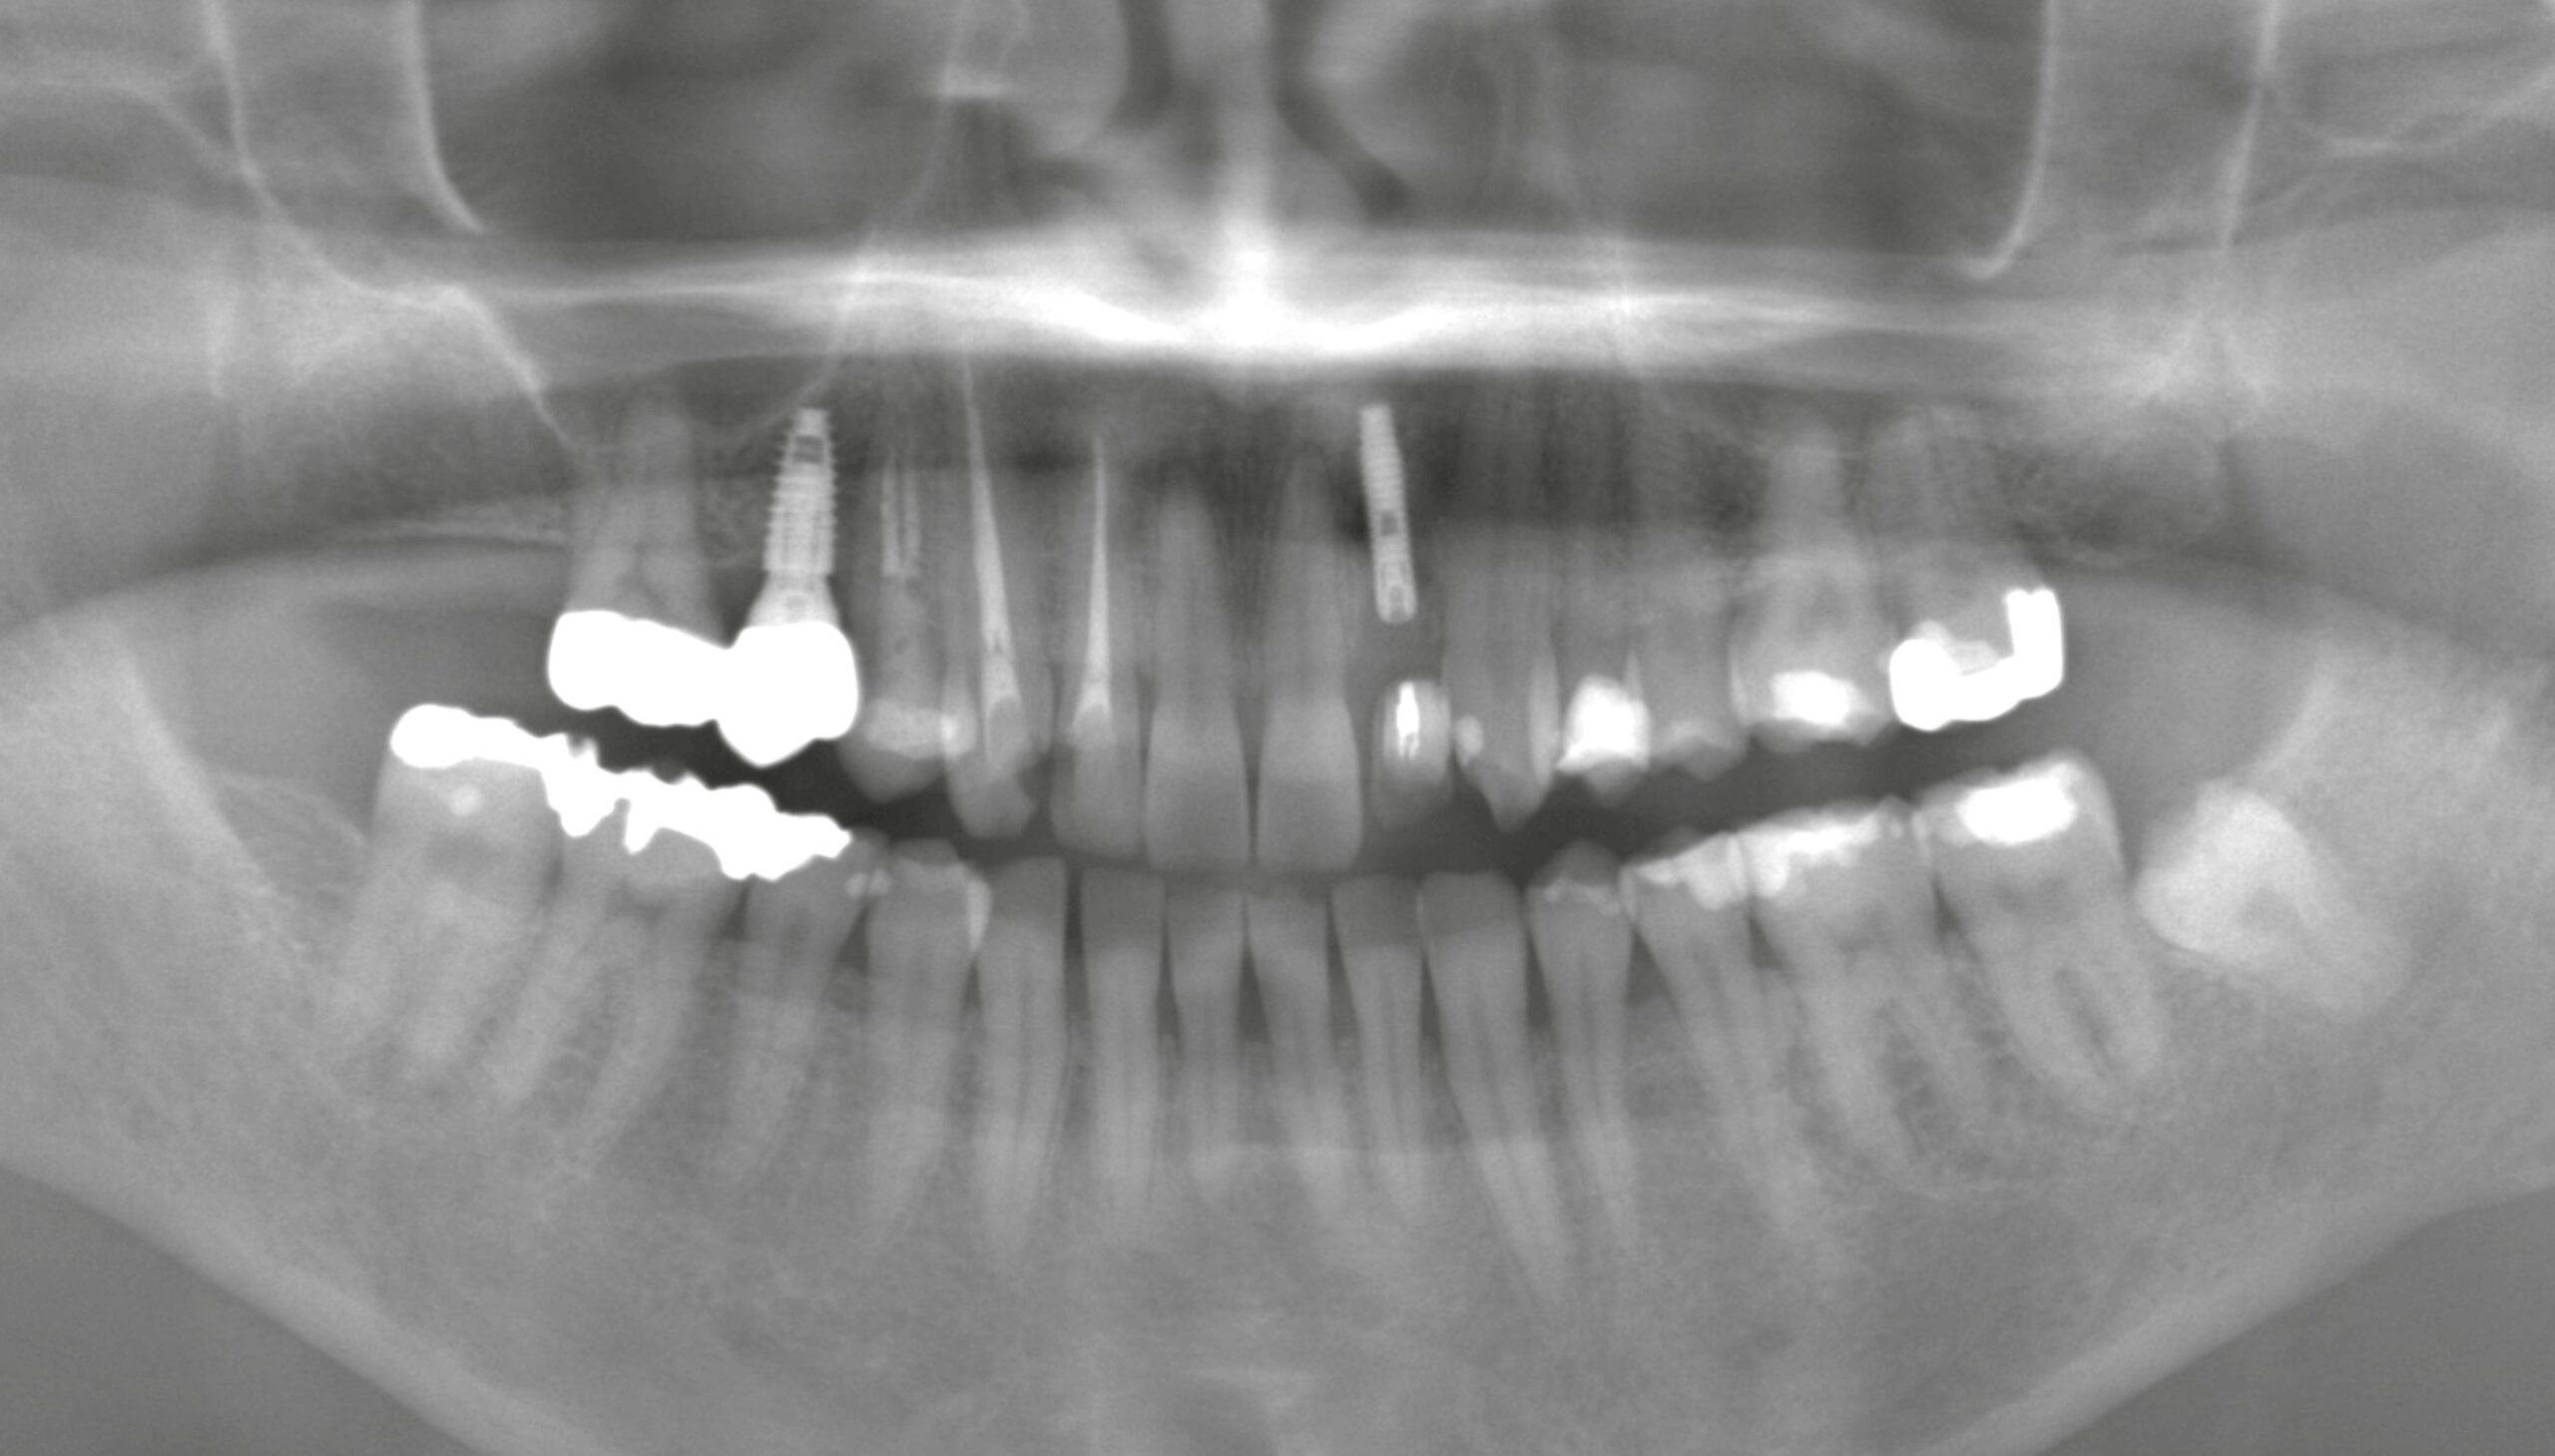

患者様は前歯の破折で来院されました。

しかし今回のように審美性や即時性が求められるケースでは、**抜歯と同時にインプラントを埋入する『抜歯即時インプラント』**が有効です。

さらに今回は、抜去した歯をトリミングして仮歯として即時に装着する方法を選択しました。

* 破折した前歯を抜歯

* 抜歯窩へ即時にインプラント埋入

* 抜去歯を加工し仮歯として装着

そのため、CTによる精密診断と適切な症例選択が非常に重要です。